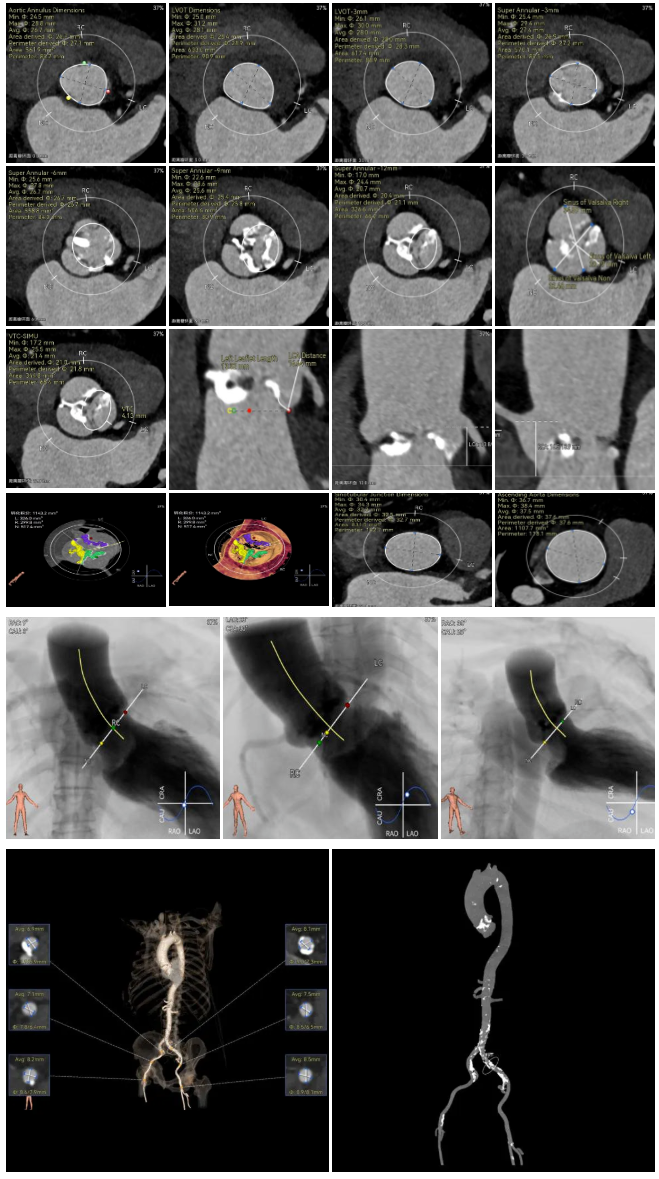

袁义强教授 河南省胸科医院(点击查看专家详细简历) 拥抱创新技术,推动心血管诊疗革新:作为医院管理者,我们团队始终把患者需求放在首位。干瓣作为TAVR的全新一代产品,其抗钙化性能预期为临床带来更卓越的耐久性,进一步延缓及降低二次手术的发生,每一个殷切期待眼神的患者身上,我们始终警醒,尽全力减少患者反复就医的痛苦,更从长远大幅节约医疗开支,让普通家庭看得起病、看好病。这不仅提升了诊疗效果,更践行了医疗惠民的初心,也多层面地减少医疗资源重复投入,为构建更经济高效的医疗体系注入动力,切实守护群众健康福祉。 孙玉梅教授 河南省胸科医院(点击查看专家详细简历) 念兹在兹,护佑患者每一刻:从医多年,我始终记得患者躺在病床上眼里饱含对健康渴求的殷切眼神,这是对医者的全心信赖——是把生命全然托付的信任,这份沉甸甸的情意,怎能辜负?选择什么手术策略,选择什么产品,医者需要给到专业意见的同时也需要听取患者的内心需求,既要保证当下手术的顺利成功,术后的快速恢复,更要为患者的长远生活兜底。Prostyle A 在这例重度钙化患者身上,既实现了术中安全植入、术后即刻改善,长久的抗钙化性能预期可以护航患者长期的生活。这份 “即刻与长久” 的平衡,正是我们一切从患者出发的初心写照,唯愿每一个细节里,都藏着让患者踏实的温度。 患者病史 主诉:间断胸闷、气促3年,加重两天。 既往史:平素健康状况良好。16 年前出现言语不清,就诊于当地医院,诊断为“脑梗死”给予药物治疗后症状好转。 术前 CT:Type1型(R-N)二叶瓣,右无交界存在钙化脊、粘连融合,极重度钙化,钙化集中在右无交界及三窦瓣叶边缘。 瓣环径27.1mm,LVOT28.9mm,瓣上3mm、6mm、9mm、12mm限制逐渐加重,从27mm逐渐缩窄至21mm。VTC空间较小,有一定冠脉风险。外周入路散在钙化、集中在双侧髂动脉与右股穿刺点后壁、双侧入路无明显迂曲,右股动脉内径可、低分叉。 手术策略 推荐右侧股动脉为主入路,瓣环27.1mm,Type1型(R-N)二叶瓣,右无交界存在钙化脊、粘连融合,极重度钙化,建议使用20mm球囊预扩,预装可回收AV23主动脉瓣膜,初始定位推荐真实瓣环上5mm超高位释放,释放时卸张力使瓣膜自然下滑至约瓣上1mm,利用瓣上限制固定瓣膜,提高封堵区封堵瓣上交界处,释放至工作位观察瓣膜情况决定是否回收。 手术过程 左右冠置入导丝进行冠脉保护 20号球囊预扩无明显腰征微量返流 初始定位 80%工作位观察 20号球囊后扩无明显腰征微量返流 术后造影:瓣膜形态好,有少量瓣周漏,冠脉造影无堵塞 术后超声:瓣膜形态好,有少量瓣周漏,平均跨瓣压差5mmHg Prostyle A®预装干瓣——“稳定支撑”助力临床最优化解决方案: 1. 平衡的径向支撑力:Prostyle A®综合设计带来平衡的径向支撑力,释放张力小,稳定贴靠,轻松应对高钙化病变; 2. Micro-EX™专利抗钙化技术:金仕生物专利抗钙化技术运用纳米技术去除组织内的细胞碎片和磷脂,封闭游离醛基,从根本上阻断了瓣膜钙化的多项因素,显著提升了瓣膜的耐久性;同时,相比较传统戊二醛保存方式,干式存储最大限度的保留心包的亲水亲油平衡,还原组织天然曲柔性,进一步保障了瓣叶开合,保证长期耐久性; 3. Prostyle A®平衡收腰设计:该例患者存在冠脉风险,Prostyle A®环上瓣及平衡的收腰设计,术后冠脉造影无堵塞,保证了有效瓣口面积的同时,带来更优异的血流动力学。